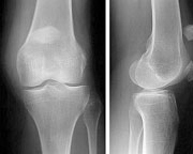

La articulación de la rodilla está formada por las partes inferior del fémur, superior de la tibia y posterior de la rótula actuando como una gran bisagra. Es la articulación más lesionada en el deportista y su tratamiento exige un gran conocimiento de la anatomía así como de la cirugía traumatológica, protésica y artroscópica.

Las fracturas en el tercio inferior del fémur son poco frecuentes. Pueden afectar al paciente joven tras un traumatismo de alta energía y al paciente anciano tras una simple caída casual debido al déficit de calcio a este nivel.

Al tratarse de fracturas articulares suponen un desafío terapéutico para el cirujano dado que la restitución de la anatomía debe ser exquisita para evitar complicaciones posteriores. Actualmente y gracias a los avances en traumatología mínimamente invasiva pueden restaurarse estas fracturas a través de pequeños abordajes percutáneos que minimizan la lesión musculocutánea favoreciendo una recuperación más rápida y confortable.

Fracturas del tercio superior de la tibia

Las fracturas en el tercio superior de la tibia suponen el 1% de todas las fracturas y el 8% de las fracturas del anciano. Están causadas por fuerzas violentas que producen desviaciones laterales sobre la rodilla. La osteoporosis en el paciente de edad facilita estas fracturas. Son lesiones que también vemos en el ámbito deportivo fundamentalmente en aquellos deportes que exigen un sobreesfuerzo de la articulación de la rodilla como el esquí, el fútbol o el patinaje. En los deportistas suelen acompañarse, además, de lesiones ligamentosas que pueden pasar desapercibidas si no se realiza una exploración exhaustiva.

El tratamiento de las fracturas del tercio superior de tibia es quirúrgico con la finalidad de devolver a la rodilla su anatomía normal para el rápido inicio de la movilidad articular. Los avances en técnica artroscópica y los nuevos implantes permiten el tratamiento de estas fracturas de una forma poco agresiva y fiable que disminuye las complicaciones postoperatorias y agiliza el tiempo de recuperación.

Fracturas de rótula

Las fracturas de rótula representan el 1% de todas las fracturas del esqueleto. Son doblemente más frecuentes en la mujer que en el hombre y, sobre todo, entre la tercera y quinta década de la vida. El impactode la rodilla en flexión sobre el suelo suele ser el mecanismo de producción habitual aunque en otras ocasiones se debe a una contracción brusca del cuádriceps. El hematoma y la imposibilidad para mover la rodilla hacen sospechar el diagnóstico que se confirma radiológicamente con una proyección lateral. El tratamiento de las fracturas de rótula se ha beneficiado de los avances en traumatología mínimamente invasiva pudiendo ser resueltas a través de pequeñas incisiones en la piel gracias a la ayuda de la artroscopia.